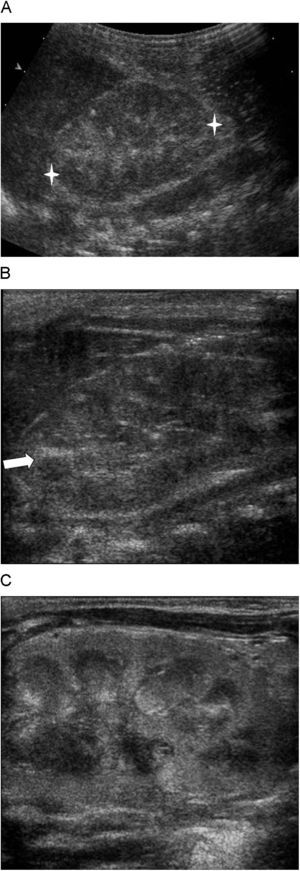

Los hallazgos ecográficos característicos incluyen nefromegalia (sobre todo en el diámetro transverso), bandas ecogénicas intramedulares (vascular streaks)3,4,6,7,9 y alteraciones de la ecogenicidad renal consistentes en hiperecogenicidad cortical en la fase hiperaguda4,15 y heterogeneidad con pérdida de la diferenciación corticomedular en la fase aguda4,16 (fig. 2).

Hallazgos ecográficos en escala de grises característicos de la trombosis venosa renal neonatal. A) Nefromegalia y ecogenicidad heterogénea con pérdida de la diferenciación corticomedular. B) Bandas ecogénicas intramedulares. C) Hiperecogenicidad cortical con aumento de la diferenciación corticomedular de la fase hiperaguda.

En los estadios iniciales, el trombo en los vasos interlobares e interlobulares aparece en forma de bandas hiperecogénicas en el estudio ecográfico. Estas bandas ecogénicas comienzan en la periferia renal, y posteriormente se extienden a los vasos intermedulares (venas interlobares). Representan la fase inicial de la trombosis venosa renal y son transitorias4. Tanto la trombosis intravascular como la hemorragia perivascular tienen un importante papel en la formación de las bandas ecogénicas intramedulares4,11, y no se deben a calcificación vascular7,17.